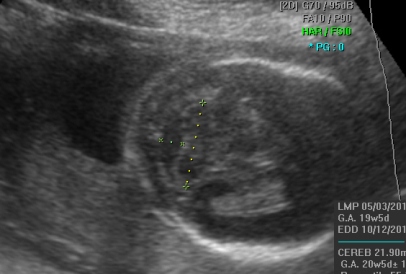

Прегледот на ултразвук во оваа фаза од бременоста најпрво опфаќа мерење на обемот и пречникот на главчето на бебето. Потоа се врши мерење на мозочните структури на бебето, што е особено значајно за откривање на некои тешки вродени малформации на централниот нервен систем. На оваа контрола се мери обемот на стомачето (AC), должината на бутната коска (FL) и должината на коската на надлактицата (хумерус). Овие мерки и нивниот меѓусебен однос даваат значајни информации за растот на бебето. Потоа внимателно се следи континуитетот на рбетниот столб, со цел исклучување на вродените малформации на рбетот (spina bifida). Понатаму може да се прикажат и внатрешните органи, како што е желудникот, мочниот меур и срцето на бебето, кое веќе има јасен четирикоморен пресек со визуелизација на двете предкомори и двете комори. Со доплер се испитува работата на срцето и протокот на крв во папочната врвка. На овој преглед се прикажува и полот на бебето, со доста јасна диференцијација на машките или женските надворешни полови карактеристики.